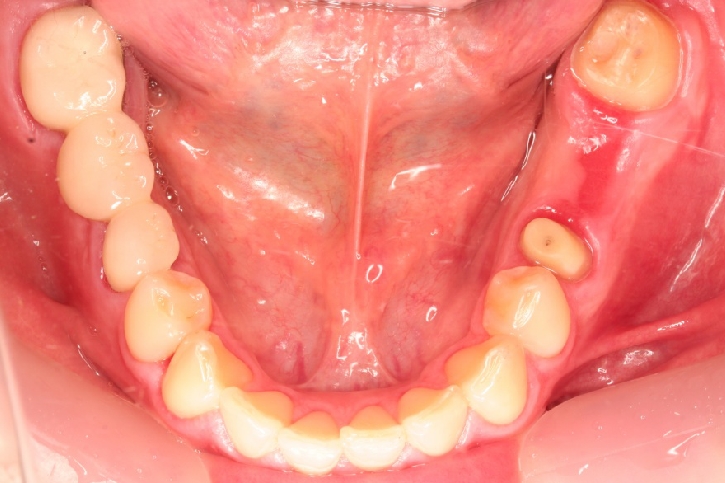

千葉市中央区 T.K様 左下567番 ポーセレンメタルボンド修復

担当歯科医師:丸林浩太郎